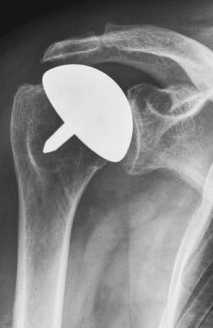

Плечевой сустав является самым подвижным суставом человека. Он состоит из плечевой кости (humerus) и суставной впадины (гленоид). При тотальном эндопротезировании замещаются оба компонента шаровидного сустава.

Как правило, при проведении операции по замене сустава шаровидная плечевая головка замещается металлическим элементом. Суставная впадина замещается мягким пластмассовым элементом, который воспроизводит функцию естественной хрящевой поверхности.

Полная замена илитотальное эндопротезирование плечевого сустава. Стержень плечевого протеза может закрепляться на цементе или бесцементно. © Gelenk-Klinik

Полная замена или тотальное эндопртезирование плечевого сустава. Стержень плечевого протеза может закрепляться на цементе или бесцементно.

Полная замена плечевого сустава или тотальное эндопротезирование плечевого сустава. Плечевой компонент зафиксирован внутри плечевой кости. Гленоидный компонент замещает суставную впадину. © Wikipedia

При полной замене плечевого сустава заменяются оба компонента сустава: плечевая головка и суставная впадина. Это самый распространенный метод замены плечевого сустава. При износе обеих поверхностей сустава, как плечевой головки так и суставной впадины, необходим полный эндопротез. При таком методе замены удаляется сегмент плечевой головки, наиболее близкий к суставу. Затем внутренняя часть (пространство костного мозга) плечевой кости подготавливается для внедрения ножки протеза.

Ножка протеза имплантируется вовнутрь кости. Одним из наиболее тяжелых осложнений при полной замене плечевого сустава является ослабление гленоидного компонента. Это ведет к возникновению боли и ограничению подвижности.